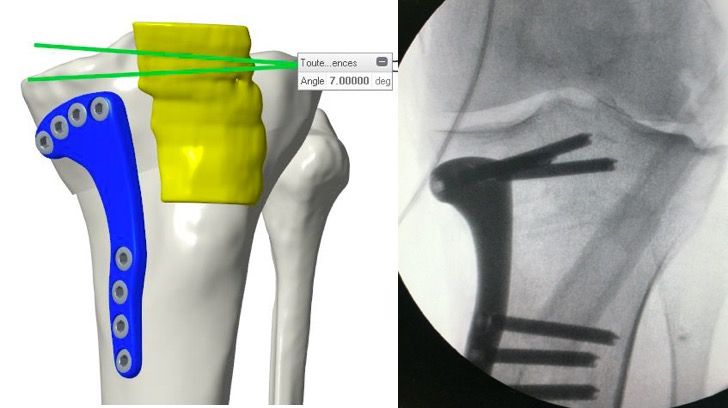

Opening Wedge and Fixation

The opening is performed by placing the spreader posterior to the MCL. Depending of the amount of opening the MCL will be tensioned and need some release. The additional tension of the MCL can be sensed easily with the fingertip. We manage the necessary release of the MCL using the pie-crusting technique. For limited amount of corrections, a small release of the posterior fibers allows sufficient lengthening and maintain integrity of the MCL to cover the osteotomy plate. The correction is performed sufficiently when the previously drilled holes in the tibia bone are fitting to the selected holes in the plate. The plate is then finally fixed to the tibia bone by using all drilled screw holes to sufficiently hold the planned correction. (Figure 12)

- Saw blade guidance to allow very accurate angulation relatively to tibial morphological parameters (Figure 7)

- Map of 6 to 8 screw holes to allow guided drilling for screw holes which will match to the screw position of the final plate after the correction (Figure 8)

- Secure the system onto the tibial bone for sawing using the 6 to 8 holes which are prepared for the future final screws position